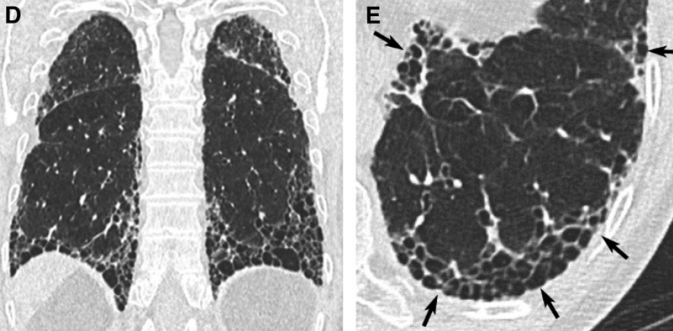

- Fibrose (reticulations, bronchiectasies de traction)

- Rayon de Miel++

- Quelque verre depoli focal (plages actives de la maladie)

- Gradient apcio-basal (= prédomine en basal)

- UIP typique (avec rayon de miel) ou probable (sans rayon de miel) = on évite une biopsie potentiellement fatale au patient